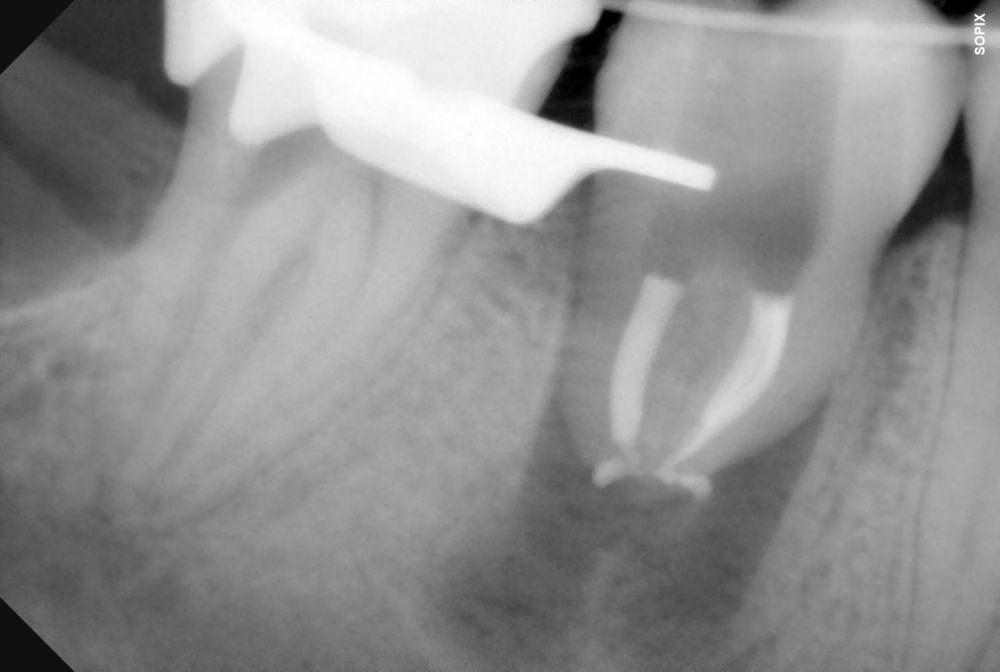

El diente donante ideal debería tener una anatomía radicular de fácil instrumentación endodóntica, y ápice abierto de al menos 1,5mm de diámetro para permitir una adecuada revascularización, con formación radicular de al menos 2/3. Así mismo, debería ser lo suficientemente pequeño para el asentamiento adecuado en el alveolo receptor, cónico, cuya extracción se pueda realizar de forma atraumática3,5,7.

El sitio receptor debe garantizar la adaptación del diente donante, se realizará un diagnóstico mediante planificación con CBCT que permita segmentar virtualmente el diente donante y llevarlo digitalmente al sitio receptor3.

Varios estudios han señalado la cronología de la cicatrización periodontal como factor determinante en el éxito de un autotransplante. Para que sucedan estos procesos es indispensable la presencia de células viables activas en la superficie radicular del diente que se va a trasplantar8-10.